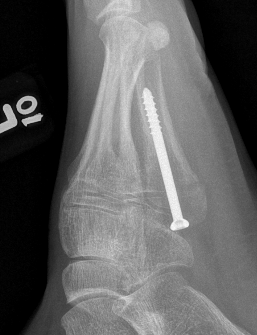

Intramedullary Screw

Screw fixation Zone 2 nonunion

Screw fixation Zone 3 nonunion

Technique

Entry point

- 5th metatarsal is not straight

- high and medial to get straight shot

- avoids plantar insertion peroneus brevis

- screw diameter 3.5 / 4.5 / 5.5 / 6.5

- screw threads must be distal to fracture site to allow compression